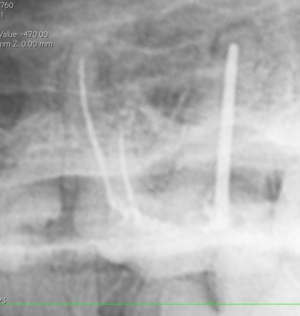

ポータブルレントゲンによる術中写真

...

術後の写真 充填( 赤ラインは根先部 )

麻酔なしのレントゲンにおいては2本が重なり一本に見えることもあります。

下記に5つの例を記載してみました。5kg / 20kg / 10kg / 5kg / 5kg

ISO 35 16mm / ISO 35 11mm / ISO 70 15.5mm